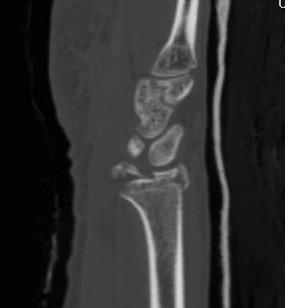

Dislocated Radiocarpal Joint CT 1Dislocated Radiocarpal Joint CT 2Dislocated Radiocarpal Joint CT 3